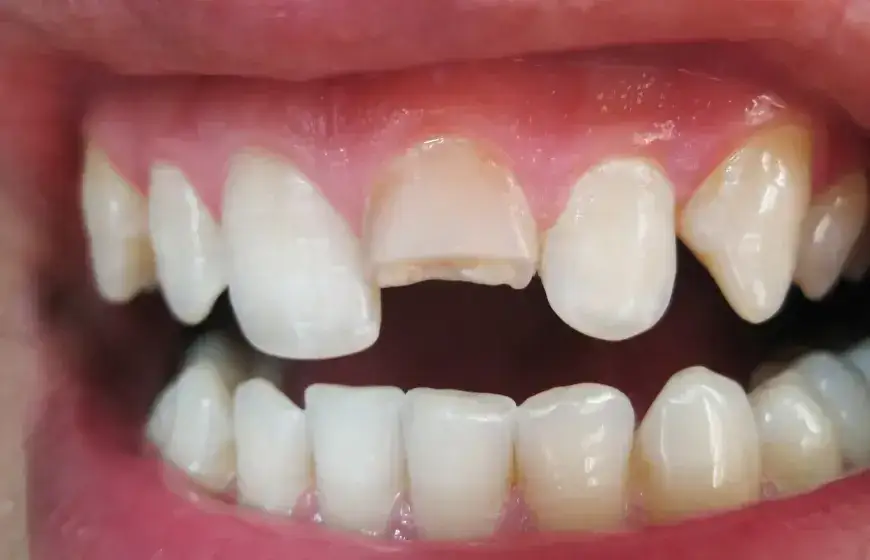

Rodzaj i położenie pęknięcia: co decyduje o rokowaniach?

Najważniejszym czynnikiem wpływającym na rokowania jest rodzaj i lokalizacja pęknięcia. Pęknięcia mogą być pionowe, poziome lub skośne. Ich położenie również ma znaczenie czy pęknięcie znajduje się na samym wierzchołku korzenia, w jego środkowej części, czy może obejmuje szyjkę zęba. Im bardziej pęknięcie jest rozległe i im bliżej znajduje się ujścia kanału korzeniowego, tym trudniejsze może być jego leczenie i tym gorsze mogą być rokowania.

Pionowe czy poziome? Które złamanie daje większe nadzieje?

Generalnie, pęknięcia pionowe, zwłaszcza te biegnące przez całą długość korzenia i sięgające aż do kości, są trudniejsze do leczenia i często prowadzą do konieczności usunięcia zęba. Dają one otwartą drogę dla bakterii do tkanek okołowierzchołkowych. Z kolei niektóre pęknięcia poziome, jeśli są zlokalizowane w odpowiednim miejscu i nie obejmują całego przekroju korzenia, mogą dawać większe nadzieje na powodzenie leczenia zachowawczego lub chirurgicznego. Ważne jest jednak, aby pamiętać, że każda sytuacja jest unikalna.